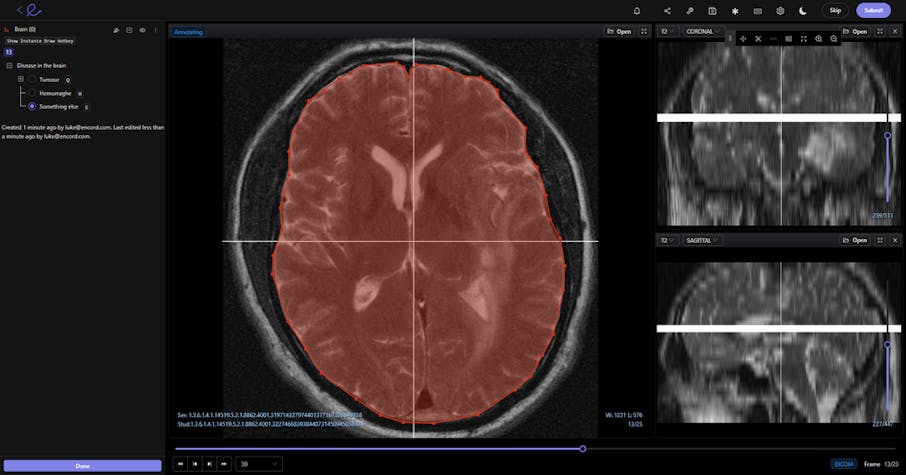

DICOM image being annotated in Encord

When annotators and data scientists talk about displaying the data “correctly”, we mean in a native format. So that when images or videos are uploaded to an AI-based computer vision annotation tool — whether in DICOM format or NIfTI format — nothing is lost.

In the best video annotation and computer vision tools, DICOM or NIfTI formatting is displayed natively. Videos of any length can be displayed and processed.

And crucially, DICOM files come with layers of patient information, such as database connections, image analysis and doctor notes, and even scheduling data for appointments. None of this information must be lost during AI-based computer vision analysis of those images.

- For example, DICOM images are used in CT, MRI, Ultrasound, and RF. Displaying these images in a native format means that annotators and healthcare professionals can accurately measure the size of tumors and other medical problems, and this information can be fed into computer vision models.